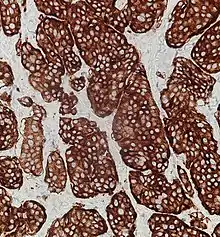

Placing a given tumor into one of these categories depends on well-defined histological features: size, lymphovascular invasion, mitotic count, Ki-67 labelling index, invasion of adjacent organs, presence of metastases and whether they produce hormones.[4][5]

Neuroendocrine tumors, despite differing embryological origin, have common phenotypic characteristics. NETs show tissue immunoreactivity for markers of neuroendocrine differentiation (pan-neuroendocrine tissue markers) and may secrete various peptides and hormones. There is a lengthy list of potential markers in neuroendocrine tumors; several reviews provide assistance in understanding these markers.[70][60] Widely used neuroendocrine tissue markers are various chromogranins, synaptophysin and PGP9.5. Neuron-specific enolase (NSE) is less specific.[1][8] The nuclear neuroendocrine marker insulinoma-associated protein-1 (INSM1) has proven to be sensitive as well as highly specific for neuroendocrine differentiation.[71]